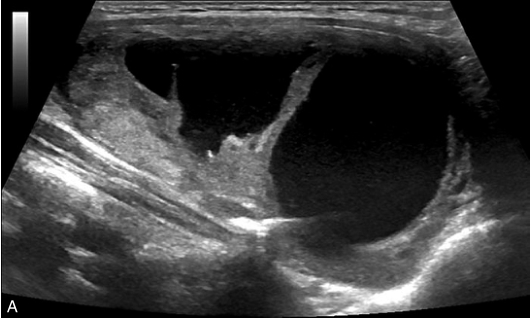

甲状腺囊肿常规超声表现为边界清晰、形态较规则的无回声结节,内可见点状强回声,后伴“彗星尾”征,CDFI内部无明显血流信号,见图1-3-1。

图1-3-1 甲状腺囊肿常规超声声像图

A.甲状腺左叶纵切面;B.CDFI血流图